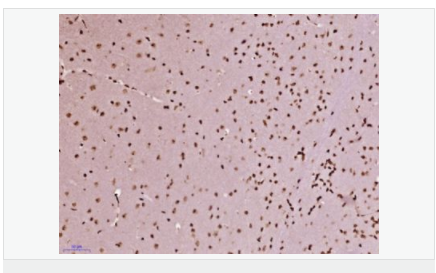

細(xì)胞定位細(xì)胞核

產(chǎn)品介紹Zinc finger protein-like 1 is a 310 amino acid single-pass membrane protein with two zinc fingers at the N-terminus, the second of which is likely a RING domain. The RING domain, which is a 40-60 amino acid, cysteine-rich domain that binds two atoms of zinc, plays a key role in the ubiquitination pathway. The presence of zinc finger-like and leucine zipper-like domains in ZFPL1 suggests a role in DNA binding and transcriptional regulation. ZFP1 is widely expressed in the golgi apparatus and is involved in maintaining golgi structure and regulating the rate of cargo transport.

Required for cis-Golgi integrity and efficient ER to Golgi transport. Involved in the maintenance of the integrity of the cis-Golgi, possibly via its interaction with GOLGA2/GM130.

Subcellular Location: